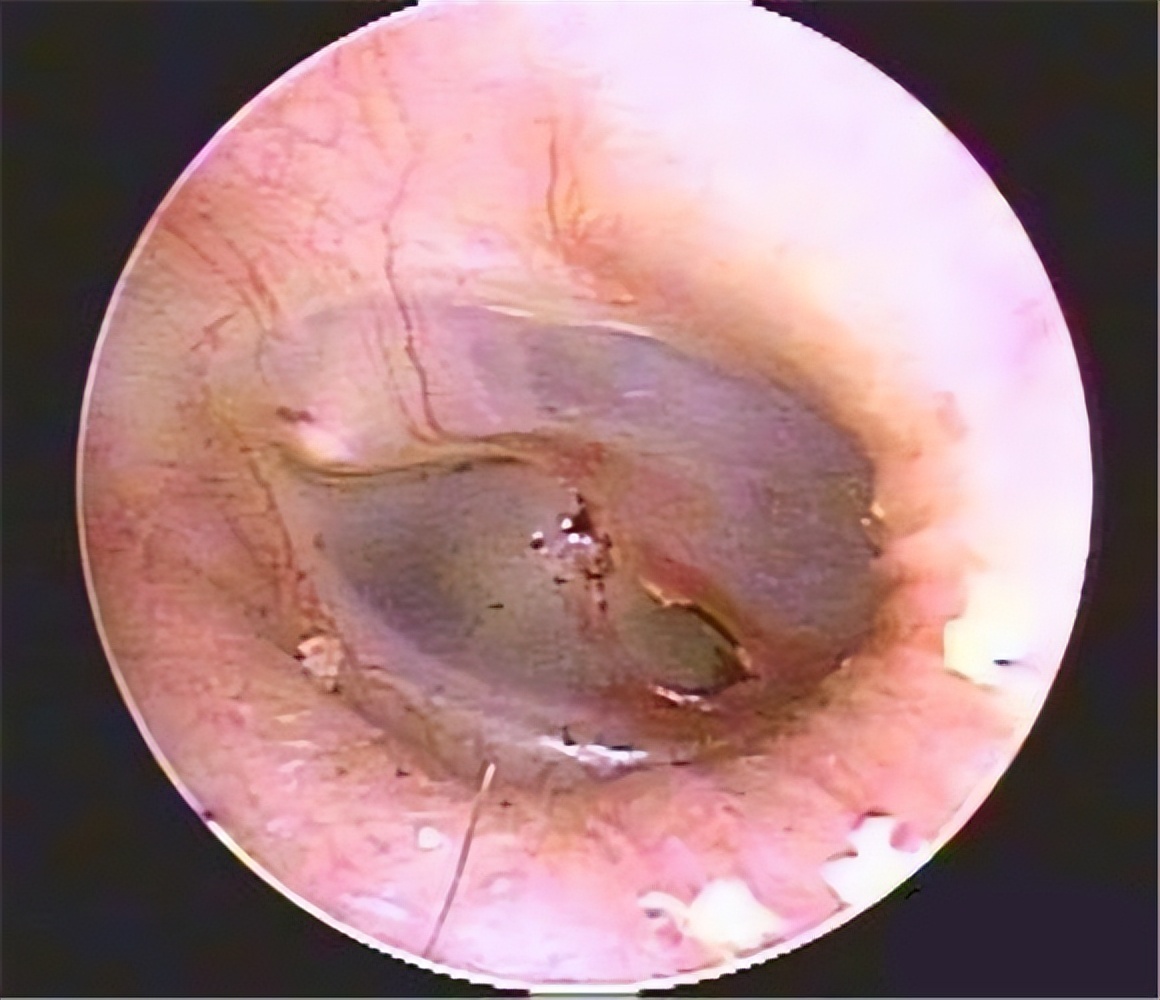

鼓膜外伤的临床表现是突然的耳痛、耳鸣、听力下降,有时可见少量的出血及耳朵的闷塞感,严重者内耳受损,出现眩晕、恶性及耳聋。检查可见鼓膜穿孔,多不规则,穿孔边缘有少量血迹,若有水样液体流出,提示颅底骨折引起的脑脊液耳漏。听力学检查为传导性或混合性耳聋。